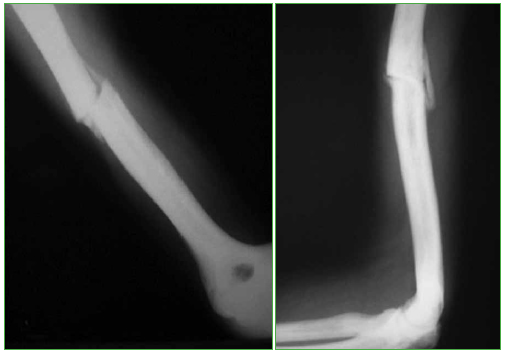

Mujer de 43 años, oficinista, con politraumatismos por un accidente automovilístico de alta energía: fractura subtrocantérica de fémur derecho, fractura del tercio medio del húmero derecho (Figura 1), fracturas de cúbito y radio distales derechos, y múltiples fracturas costales. Sin lesión nerviosa ni vascular. No tiene antecedentes familiares ni personales de relevancia.

Figura 1.

Radiografías de diáfisis del húmero derecho obtenidas el día del traumatismo. Se observa una fractura transversal.